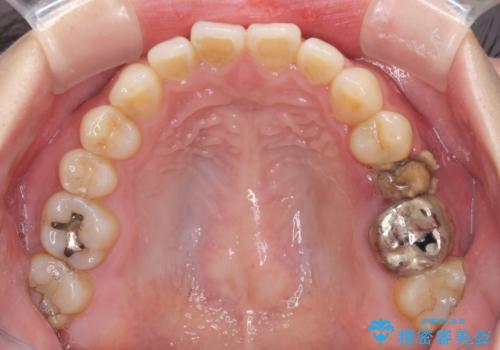

- 他院で大きな虫歯の歯を引っ張り出す治療中、あまりにも異臭がするとのことで来院された患者様です。

診査したところ、虫歯が広範囲で、粗造になった歯の表面に汚れがこびりついていました。また、歯根の半分以上の深さにまで亀裂が生じており、保存は不可能と診断しました。